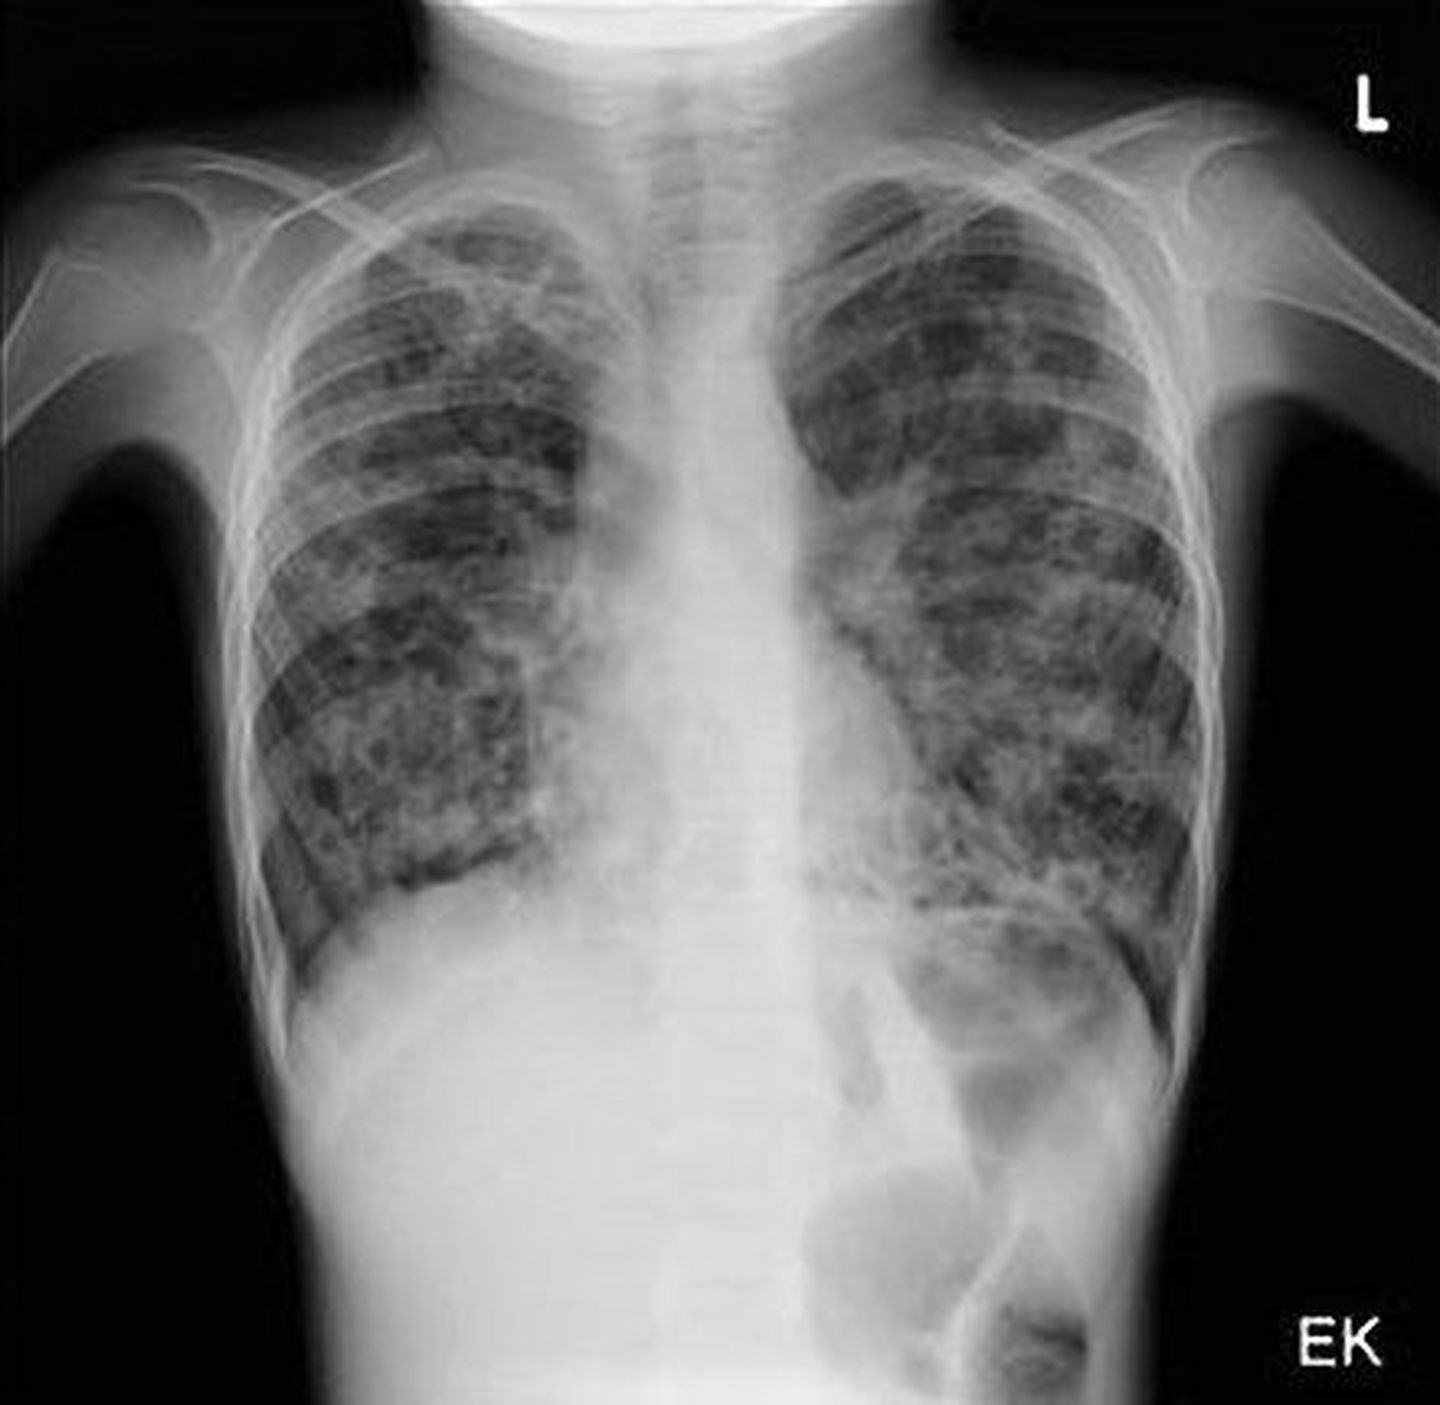

Cystic fibrosis (often abbreviated as CF, also called mucoviscidosis or fibrocystic disease of the pancreas) is an autosomal recessive genetic disorder. The disease is caused by a mutation in the CF gene (chromosome 7), which codes for a protein that functions as a chlorine channel called CFTR (Cystic Fibrosis Transmembrane conductance Regulator). Cystic fibrosis is the most common fatal inherited genetic disease in the Caucasoid population. This genetic mutation is fatal, those born with it have a very low life expectancy that can increase if drug therapy is carried out consistently. Unfortunately, today there is no cure, other than lung transplantation. Usually the luckiest individuals are able to reach the age of 30-35 without resorting to a transplant which in many cases does not work as the body rejects it.